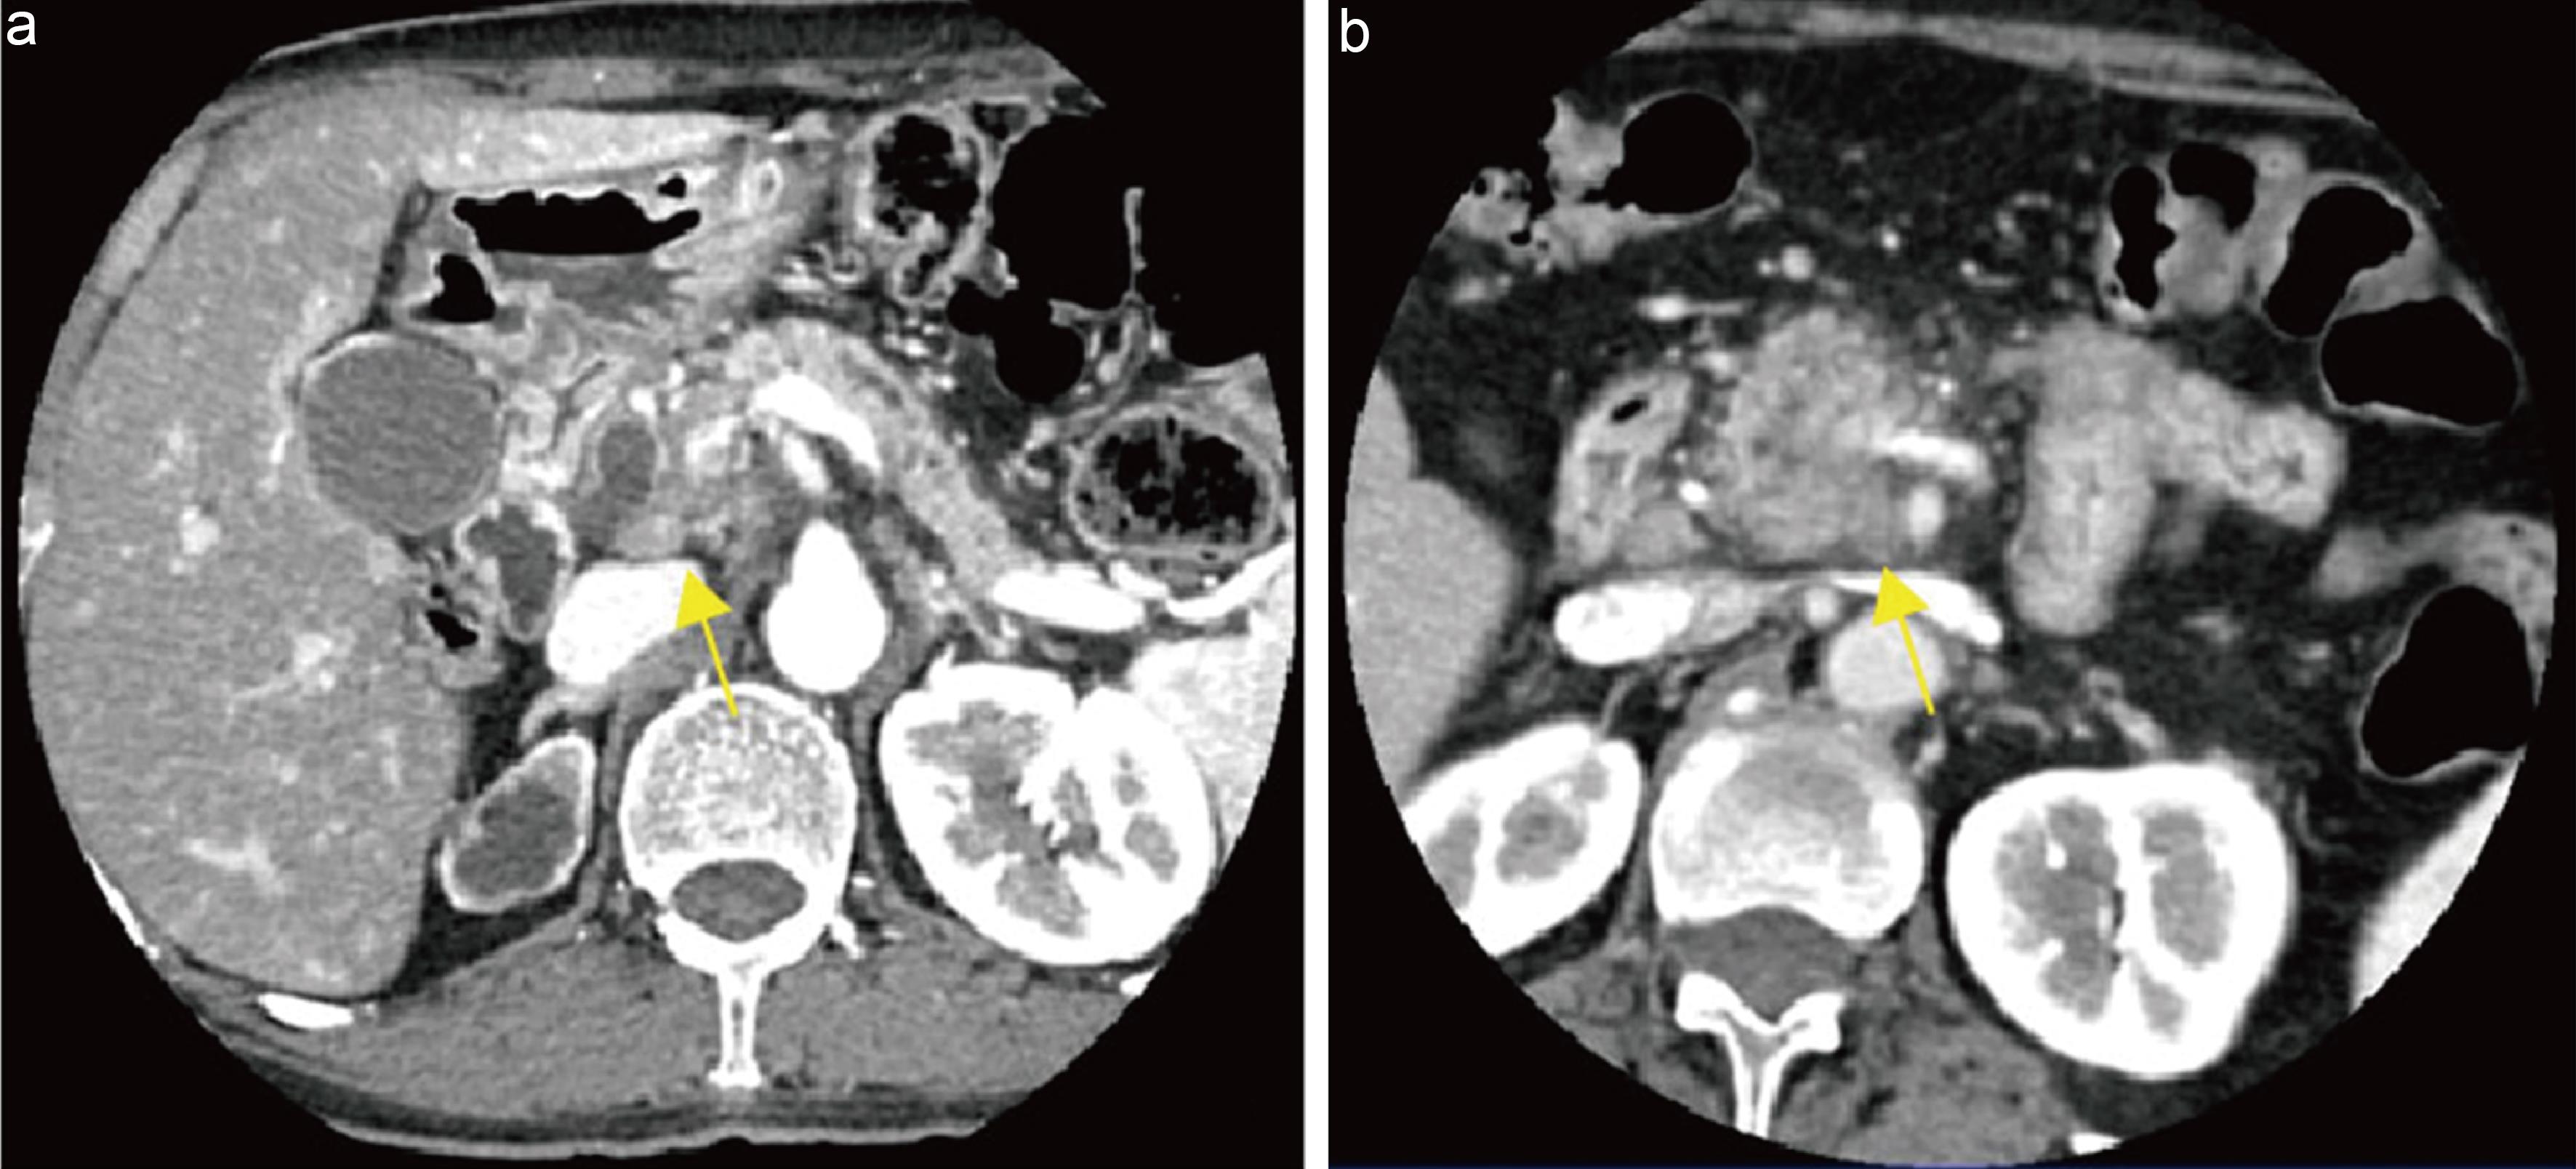

Explanation: Alcohol and gallstones are the most important etiologies of acute pancreatitis. Pancreatic cancer is a relatively uncommon cause, with an incidence of 0.9% to 3.6%.94 Mujica et al.95 hypothesized possible mechanisms by which pancreatic cancer induces acute pancreatitis, including mechanical obstruction of the pancreatic duct, ischemia caused by malignant tumor cells obstructing blood vessels, and direct activation of pancreatic enzymes by tumor tissue. The presence of obstructive pancreatitis is assessed based on suspicious masses, main pancreatic duct interruption with upstream ductal dilation, pancreatic enlargement upstream, blurring of peripancreatic fat planes, and stranding edema.96,97 Studies have found that 59% of pancreatic cancer cases were initially misdiagnosed as acute pancreatitis due to inflammatory changes masking underlying masses or secondary signs.98 Tummala et al.99 studied 218 patients with acute pancreatitis undergoing EUS-FNA and identified 38 cases of pancreatic cancer diagnosed promptly after the first episode of acute pancreatitis, with a resection rate of 39%, thereby improving patient survival. Therefore, in patients with acute pancreatitis after excluding common causes such as alcohol and gallstones, careful evaluation of pancreatic imaging is warranted to identify potential underlying malignancy,50,99,100 and this should be explicitly stated in imaging reports (Fig. 5).

Pancreatic cancer with surrounding obstructive inflammation.

Fig. 5  Pancreatic cancer with surrounding obstructive inflammation.

Axial arterial late-phase computed tomography (CT) image shows a hypodense mass in the pancreatic body and tail (white arrow), with patchy peripancreatic inflammatory infiltration (yellow arrow).